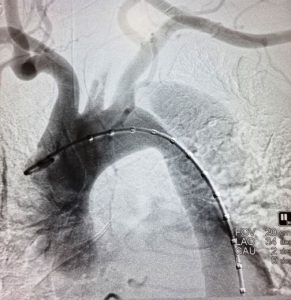

In dissection, there is a tear inside the aorta. With the advancement of therapy, cases of aortic dissection are managed by stenting the aorta.

In case of this patient, there was a large tear that was extending to the artery supplying blood to the left upper limb. “Our cardiac surgery team of Dr A Sharda and Dr Chandan Kumar Raymohapatra first did carotid to carotid and carotid to left subclavian bypass. These bypass grafts prevented brain stroke and maintained blood supply to the left hand. Then the cardiology team led by Dr Anupam Jena put a covered stent inside the aorta to seal the tear,” a press release of KIMS stated.

This is a one of its kind hybrid repair of the aorta in Odisha. An untreated dissection of the aorta can create serious problems as blood gets stuck in the damaged part of the wall. As a result, the body organs, which get their blood from the aorta, might not get enough blood. This can lead to problems such as heart attack, brain damage, kidney damage, intestinal problems or inadequate blood flow to the legs or arms. If this happens, the wall of the aorta can burst open leading to internal bleeding leading to an emergency condition.